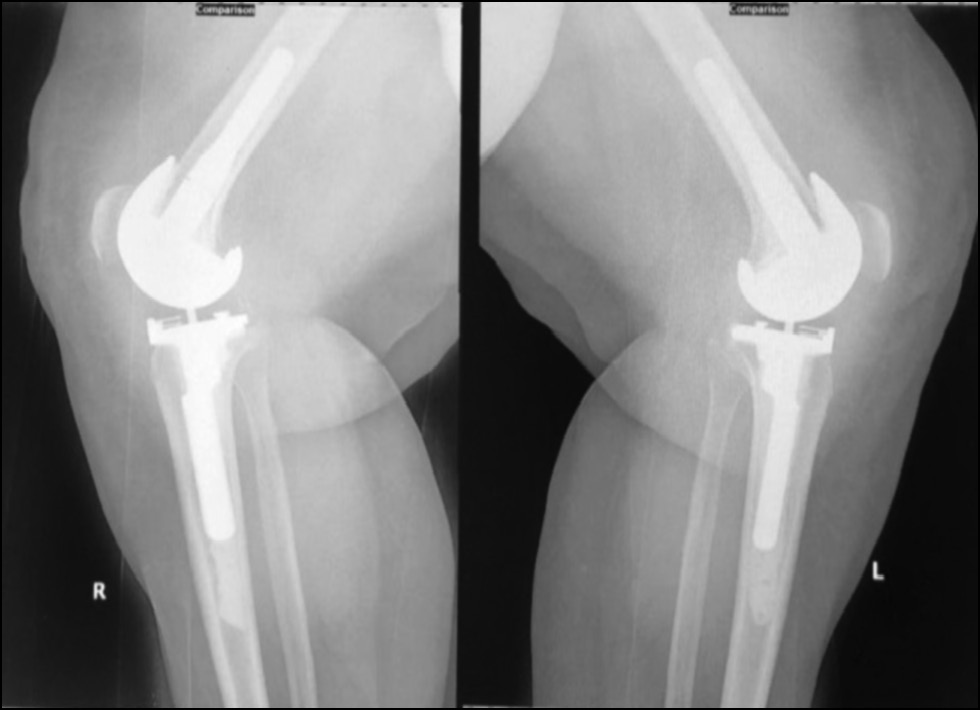

Fig. 13. Ap postoperative x-ray showing bilateral total knee arthroplasty.

Рис. 13. Послеоперационная рентгенограмма с двусторонней тотальной артропластикой коленного сустава.

Fig. 14. Lateral postoperative x-ray right and left knees showing bilateral total knee arthroplasty.

Рис. 14. Послеоперационная боковая рентгенограмма правого и левого колена, демонстрирующая двустороннюю тотальную артропластику коленного сустава.

CASE 1. PATIENT 16

Age: 64 years.

Sex: Female.

Diagnosis: Bilateral advanced knee osteoarthritis.

Procedure: Bilateral simultaneous knee arthroplasty.

Associated illnesses: Hypertension.

Postoperative follow-up: No postoperative complications were encountered.

Length of hospital stay: 6 days.

Radiological assessment (Fig. 11–14)